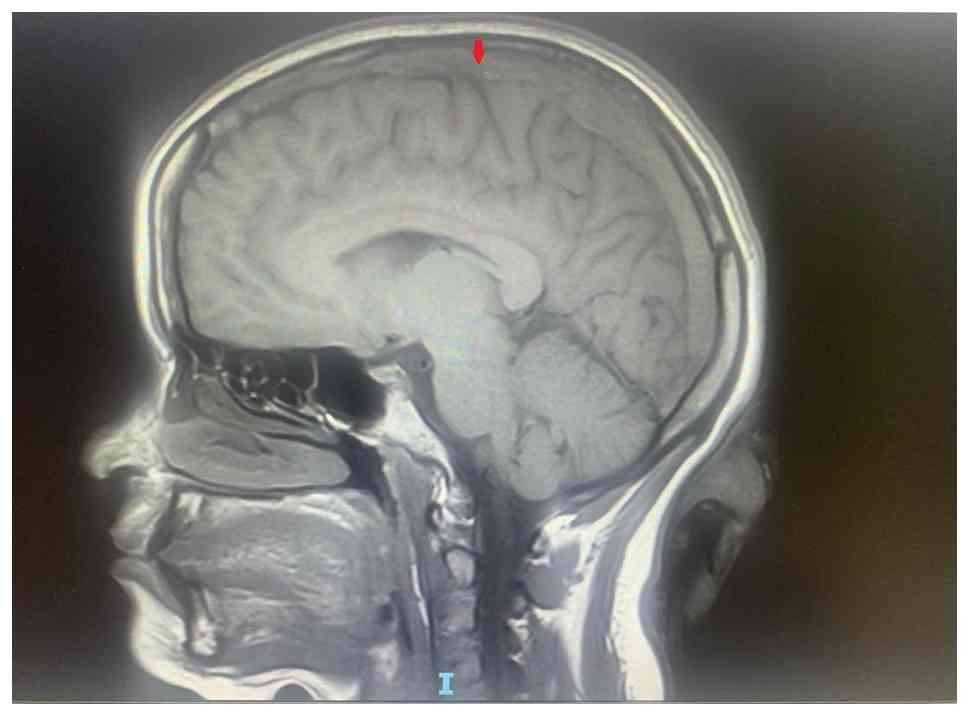

MRI FLAIR sequence axial section. The

arrow shows loss of normal flow void. Image was obtained in June

2023.

Figure 2

MRI FLAIR sequence axial section. The arrow shows loss of normal flow void. Image was obtained in June 2023.